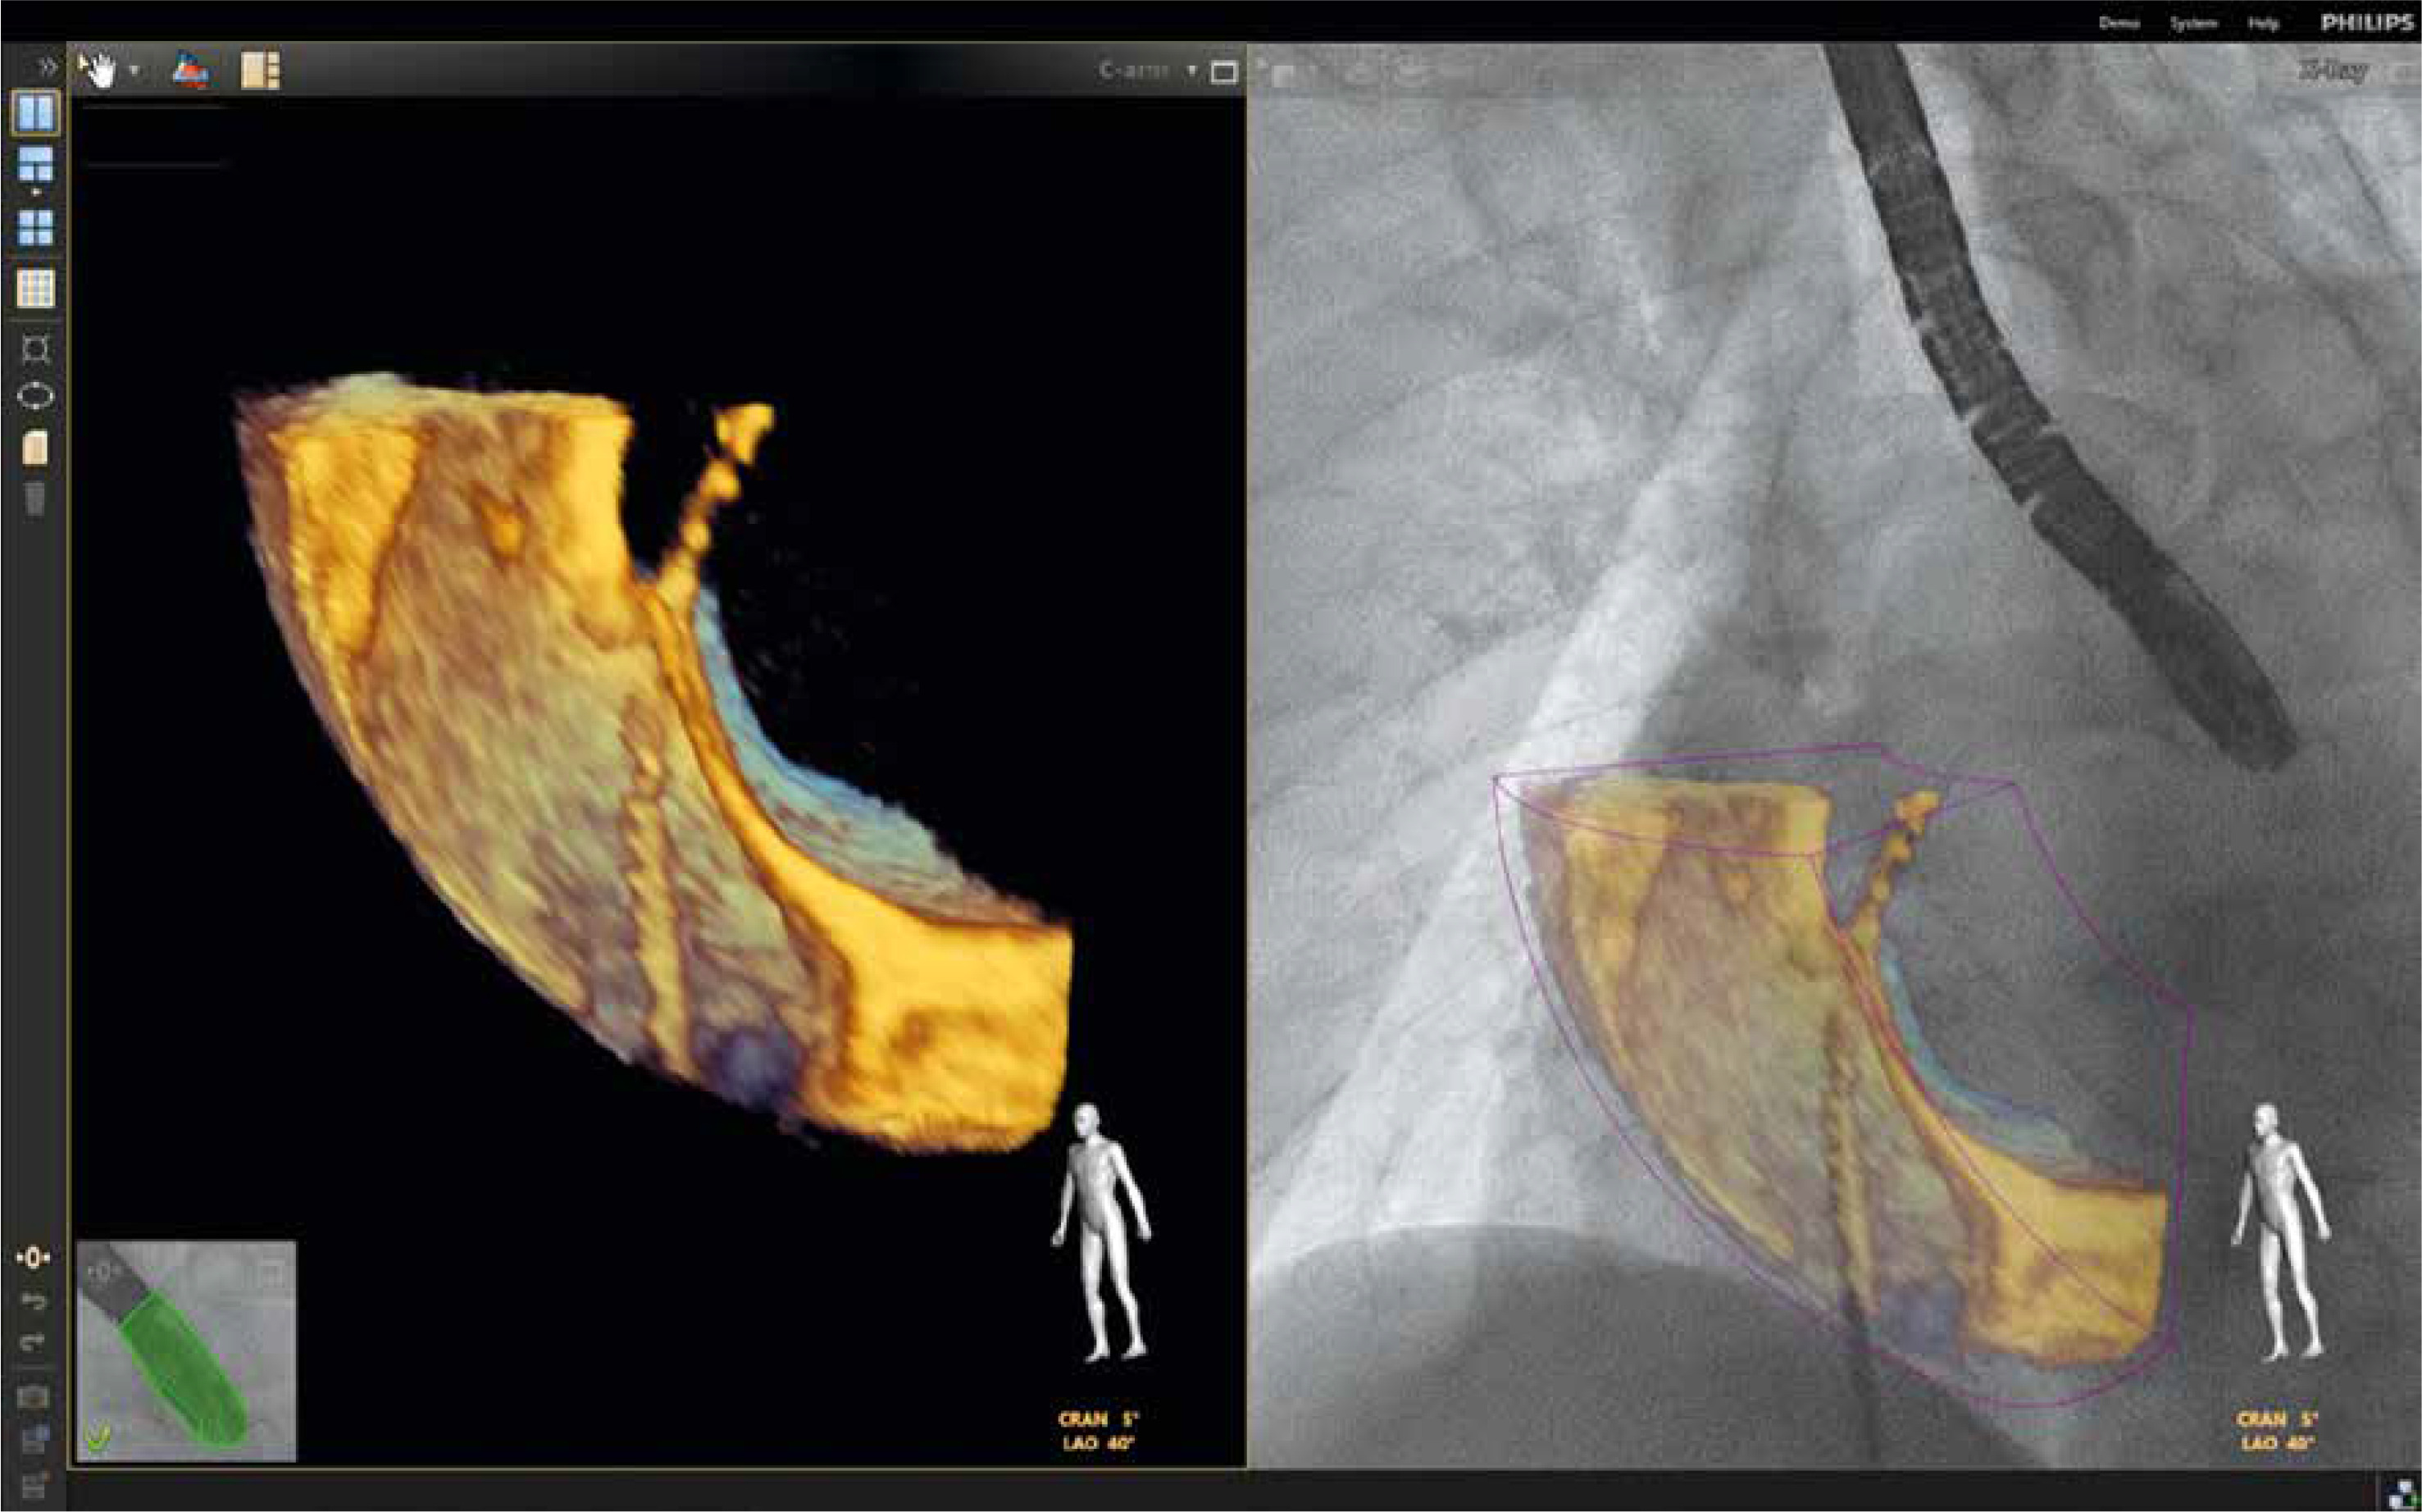

As described by Balzer et al., the EchoNavigator Release II (Philips, Best, Netherlands) system is a multimodal approach that synchronizes live echocardiography and fluoroscopy images in real time [6]. A calibration algorithm tracks the movement of the TEE probe using fluoroscopy. This is achieved through an image-based TEE probe localization algorithm and calibration procedure. After synchronization, the echocardiographic images from TEE automatically follow the motion of the fluoroscopic C-arm. The results of the coregistration process are displayed in a form that allows simultaneous visualization of an X-ray image and up to three echocardiographic views. The X-ray view shows the actual fluoroscopic image. The probe must be centered in this view to allow accurate coregistration of the probe TEE. If this is successful, the probe is displayed with a green outline; if not, e.g. after significant movement of the TEE probe, the probe is displayed with a red outline. The echo view shows images that can only be processed by the echocardiologist.

In the C-arm view, the beam path (i.e., the echocone) of the matrix array transducer is shown as a purple sector corresponding to the position of the TEE probe. Changes in the angulation, rotation, or position of the TEE probe are automatically displayed in this view. The free view displays 2D and 3D information that can be rotated, cropped, zoomed, or segmented by the operator using a sterile cover. Multiplanar reconstruction (MPR) software provides tools for 3D volume segmentation along the three axes (x, y, z) in real time or during post-processing, as well as quantitative analysis. Specific points of interest can be marked and are immediately displayed on the fluoroscopic image. These markers then serve as target points for guiding catheter manipulations. Intraoperative images of FI during LAAO are presented in Figures 1 and 2.